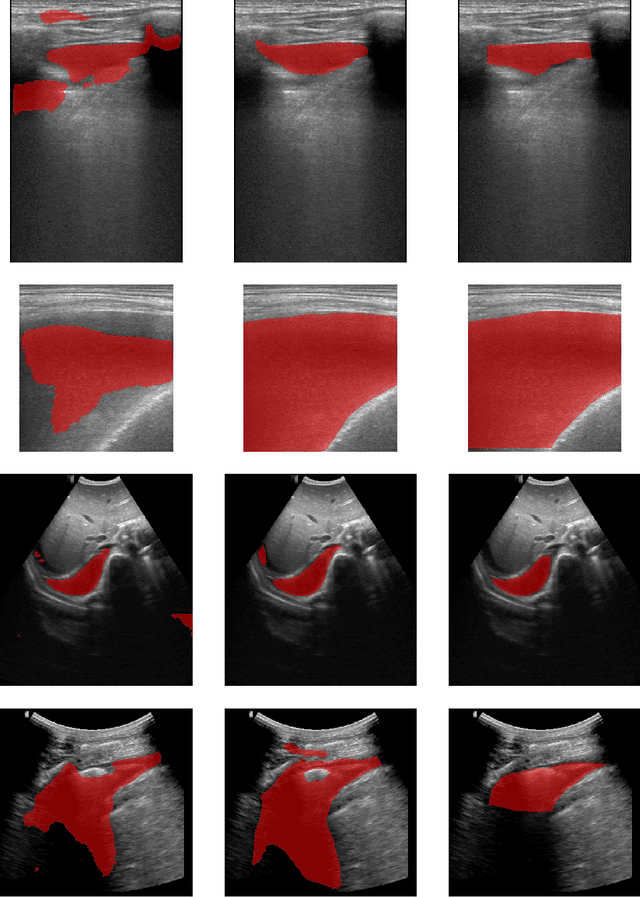

Abstract:Abnormal spleen enlargement (splenomegaly) is regarded as a clinical indicator for a range of conditions, including liver disease, cancer and blood diseases. While spleen length measured from ultrasound images is a commonly used surrogate for spleen size, spleen volume remains the gold standard metric for assessing splenomegaly and the severity of related clinical conditions. Computed tomography is the main imaging modality for measuring spleen volume, but it is less accessible in areas where there is a high prevalence of splenomegaly (e.g., the Global South). Our objective was to enable automated spleen volume measurement from 2D cross-sectional segmentations, which can be obtained from ultrasound imaging. In this study, we describe a variational autoencoder-based framework to measure spleen volume from single- or dual-view 2D spleen segmentations. We propose and evaluate three volume estimation methods within this framework. We also demonstrate how 95% confidence intervals of volume estimates can be produced to make our method more clinically useful. Our best model achieved mean relative volume accuracies of 86.62% and 92.58% for single- and dual-view segmentations, respectively, surpassing the performance of the clinical standard approach of linear regression using manual measurements and a comparative deep learning-based 2D-3D reconstruction-based approach. The proposed spleen volume estimation framework can be integrated into standard clinical workflows which currently use 2D ultrasound images to measure spleen length. To the best of our knowledge, this is the first work to achieve direct 3D spleen volume estimation from 2D spleen segmentations.

Abstract:In many low-to-middle income (LMIC) countries, ultrasound is used for assessment of pleural effusion. Typically, the extent of the effusion is manually measured by a sonographer, leading to significant intra-/inter-observer variability. In this work, we investigate the use of deep learning (DL) to automate the process of pleural effusion segmentation from ultrasound images. On two datasets acquired in a LMIC setting, we achieve median Dice Similarity Coefficients (DSCs) of 0.82 and 0.74 respectively using the nnU-net DL model. We also investigate the use of coordinate convolutions in the DL model and find that this results in a statistically significant improvement in the median DSC on the first dataset to 0.85, with no significant change on the second dataset. This work showcases, for the first time, the potential of DL in automating the process of effusion assessment from ultrasound in LMIC settings where there is often a lack of experienced radiologists to perform such tasks.

Abstract:Sickle Cell Disease (SCD) is one of the most common genetic diseases in the world. Splenomegaly (abnormal enlargement of the spleen) is frequent among children with SCD. If left untreated, splenomegaly can be life-threatening. The current workflow to measure spleen size includes palpation, possibly followed by manual length measurement in 2D ultrasound imaging. However, this manual measurement is dependent on operator expertise and is subject to intra- and inter-observer variability. We investigate the use of deep learning to perform automatic estimation of spleen length from ultrasound images. We investigate two types of approach, one segmentation-based and one based on direct length estimation, and compare the results against measurements made by human experts. Our best model (segmentation-based) achieved a percentage length error of 7.42%, which is approaching the level of inter-observer variability (5.47%-6.34%). To the best of our knowledge, this is the first attempt to measure spleen size in a fully automated way from ultrasound images.